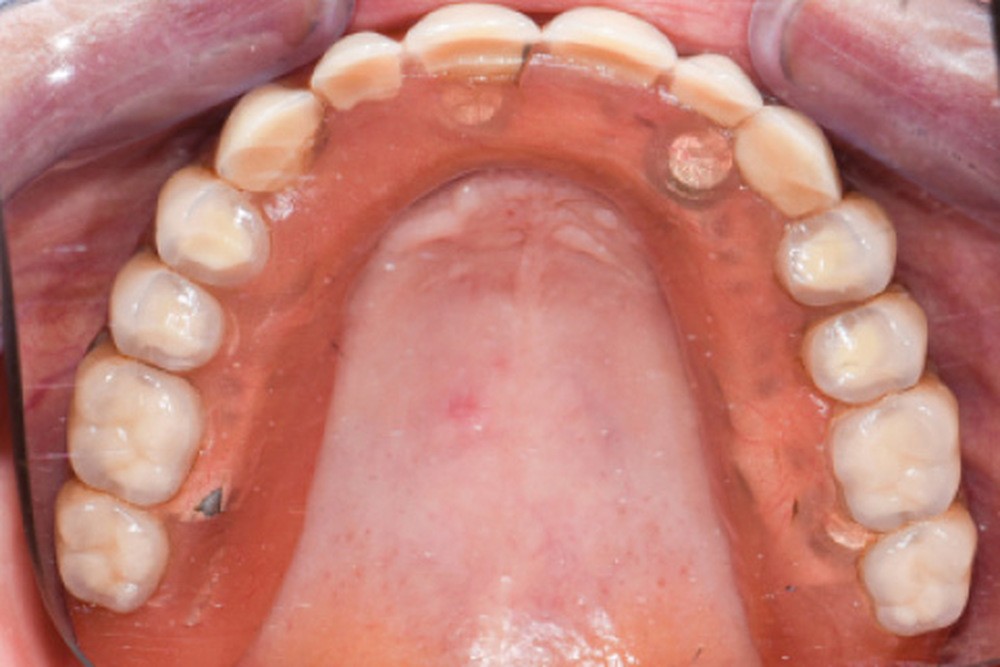

Une patiente de 65 ans consulte pour la perte d’adaptation de sa PACSI lors de la mastication. L’interrogatoire médical ne révèle aucune pathologie ni traitement médicamenteux. La patiente mentionne ne pas fumer et est sérieuse sur le plan prophylactique. Cependant, depuis quelque temps, elle se plaint d’une difficulté à mastiquer associée à une mobilité de sa prothèse et une usure des dents prothétiques (fig. 1a à e).

Une réhabilitation par PACSI maxillaire a été réalisée dix ans auparavant sur 5 implants en place de 13, 12, 21 et sur 24 et 26 (fig. 2a et b). Dans le cadre du plan de traitement initial, 6 implants avaient été indiqués. L’un d’entre eux, en position distale dans le secteur I, n’a jamais été ostéointégré. La patiente ne souhaitant plus de chirurgie, il avait donc été décidé de réaliser une prothèse sur 5 implants. La barre est directement connectée aux implants. À la mandibule, la patiente présente également une PACSI sur 2 implants associés à 2 piliers Locator®.